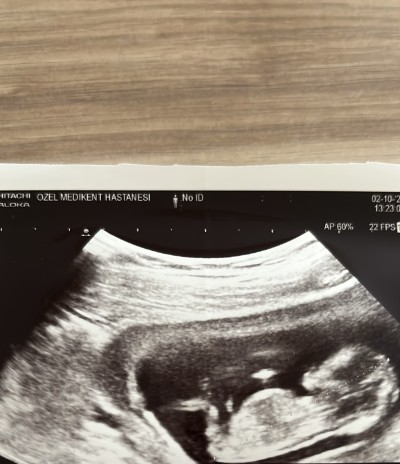

Kızlar cinsiyet tahmini yapar mısınız çok merak ediyorum ;(

Kıza benzettim canım

Ay inşallah bugün kontrolde %90 erkek dedi ama pek inanamadım

Erkek  nubi dik çünkü hayırlısı olsun ins